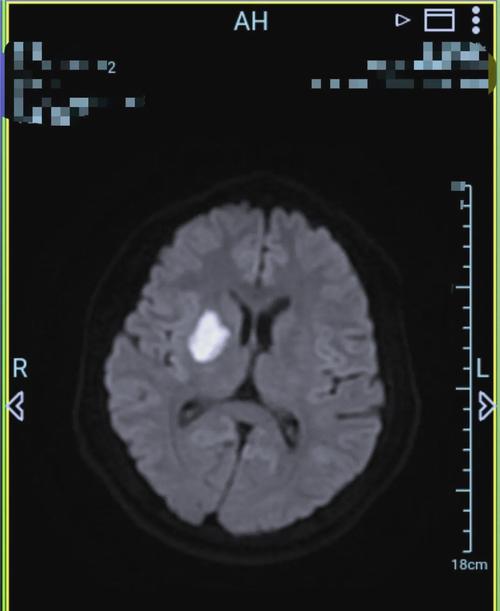

- 关键提示: 如果患者高度疑似脑梗(如突发口角歪斜、肢体无力、言语不清),但CT显示正常,医生会高度怀疑,并立即安排头颅MRI(磁共振)检查,特别是DWI序列,能更早、更准确地发现梗死病灶。

第二步:寻找“低密度影”——急性期(发病6-24小时后)

- 影像表现: 随着时间推移,缺血区域的脑细胞开始坏死、水肿,细胞内水分增多,密度逐渐降低,CT上会开始出现边界不清的、片状的低密度影。

- 医生解读: 这就是典型的脑梗死CT征象,低密度灶的位置和大小决定了梗死血管的分布和神经功能缺损的严重程度。